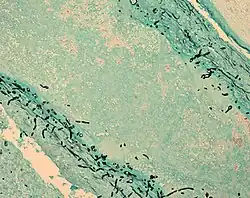

| Fungus (black) in brain tissue | |